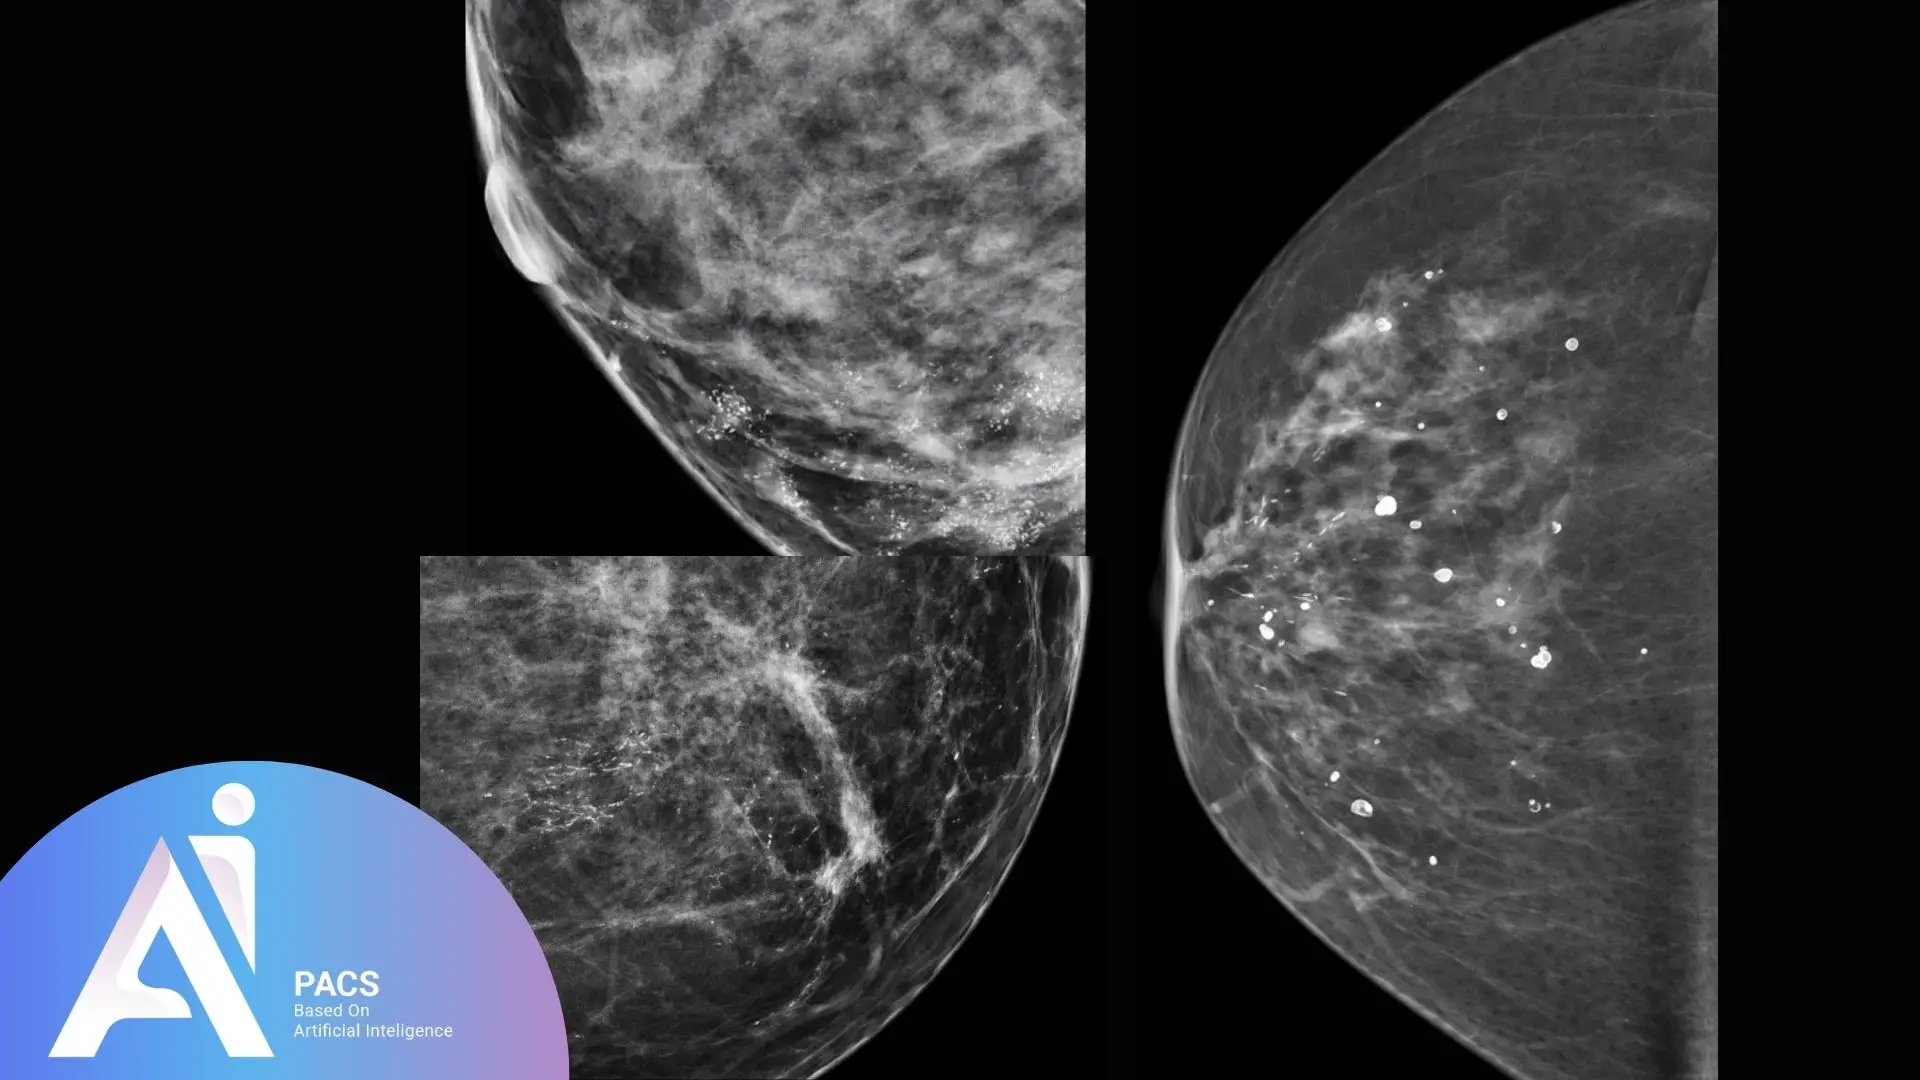

What are microcalcifications?

Microcalcifications are tiny deposits of calcium that form within breast tissue. These specks are often too small to feel during a physical exam but can be detected through imaging. While most microcalcifications are benign, specific patterns may indicate underlying conditions, including early signs of breast cancer.

Mammograms are susceptible imaging tools designed to detect subtle changes in breast tissue, including microcalcifications. The high-resolution images reveal these calcium deposits, allowing radiologists to evaluate their patterns and identify potential abnormalities that may require further investigation.

Suspicious or malignant microcalcifications

Suspicious microcalcifications may suggest abnormal changes, such as ductal carcinoma in situ (DCIS) or invasive breast cancer. These often appear in clusters or irregular patterns and may vary in shape and size. Their presence frequently prompts additional imaging or a biopsy for accurate diagnosis.

Critical differences in patterns and appearance

The appearance and arrangement of microcalcifications play a crucial role in determining their significance:

- Benign: Scattered, round, or smooth-edged deposits.

- Suspicious: Tight clusters, linear patterns, or irregular shapes.

Radiologists analyze these differences using the BI-RADS system to decide if further testing is needed.